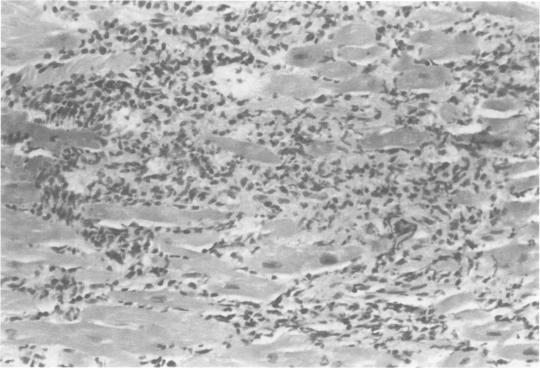

Many patients who undergo cardiac transplantation do so as a result of end-stage dilated cardiomyopathy (DC). Little is known about the causes of this condition, but long-term follow-up studies reveal a high incidence of DC in patients who have had acute viral myocarditis. The following article examines the role of myocarditis as a precursor of DC and discusses the possible etiology of myocarditis-based on animal experiments and clinical studies-as well as methods of diagnosis and treatment.

许多接受心脏移植的患者是由于终末期扩张型心肌病(DC)而进行移植的。人们对这种疾病的病因知之甚少,但长期随访研究显示,患有急性病毒性心肌炎的患者中DC的发病率很高。以下文章探讨了心肌炎作为DC前驱疾病的作用,并基于动物实验和临床研究讨论了心肌炎可能的病因,以及诊断和治疗方法。